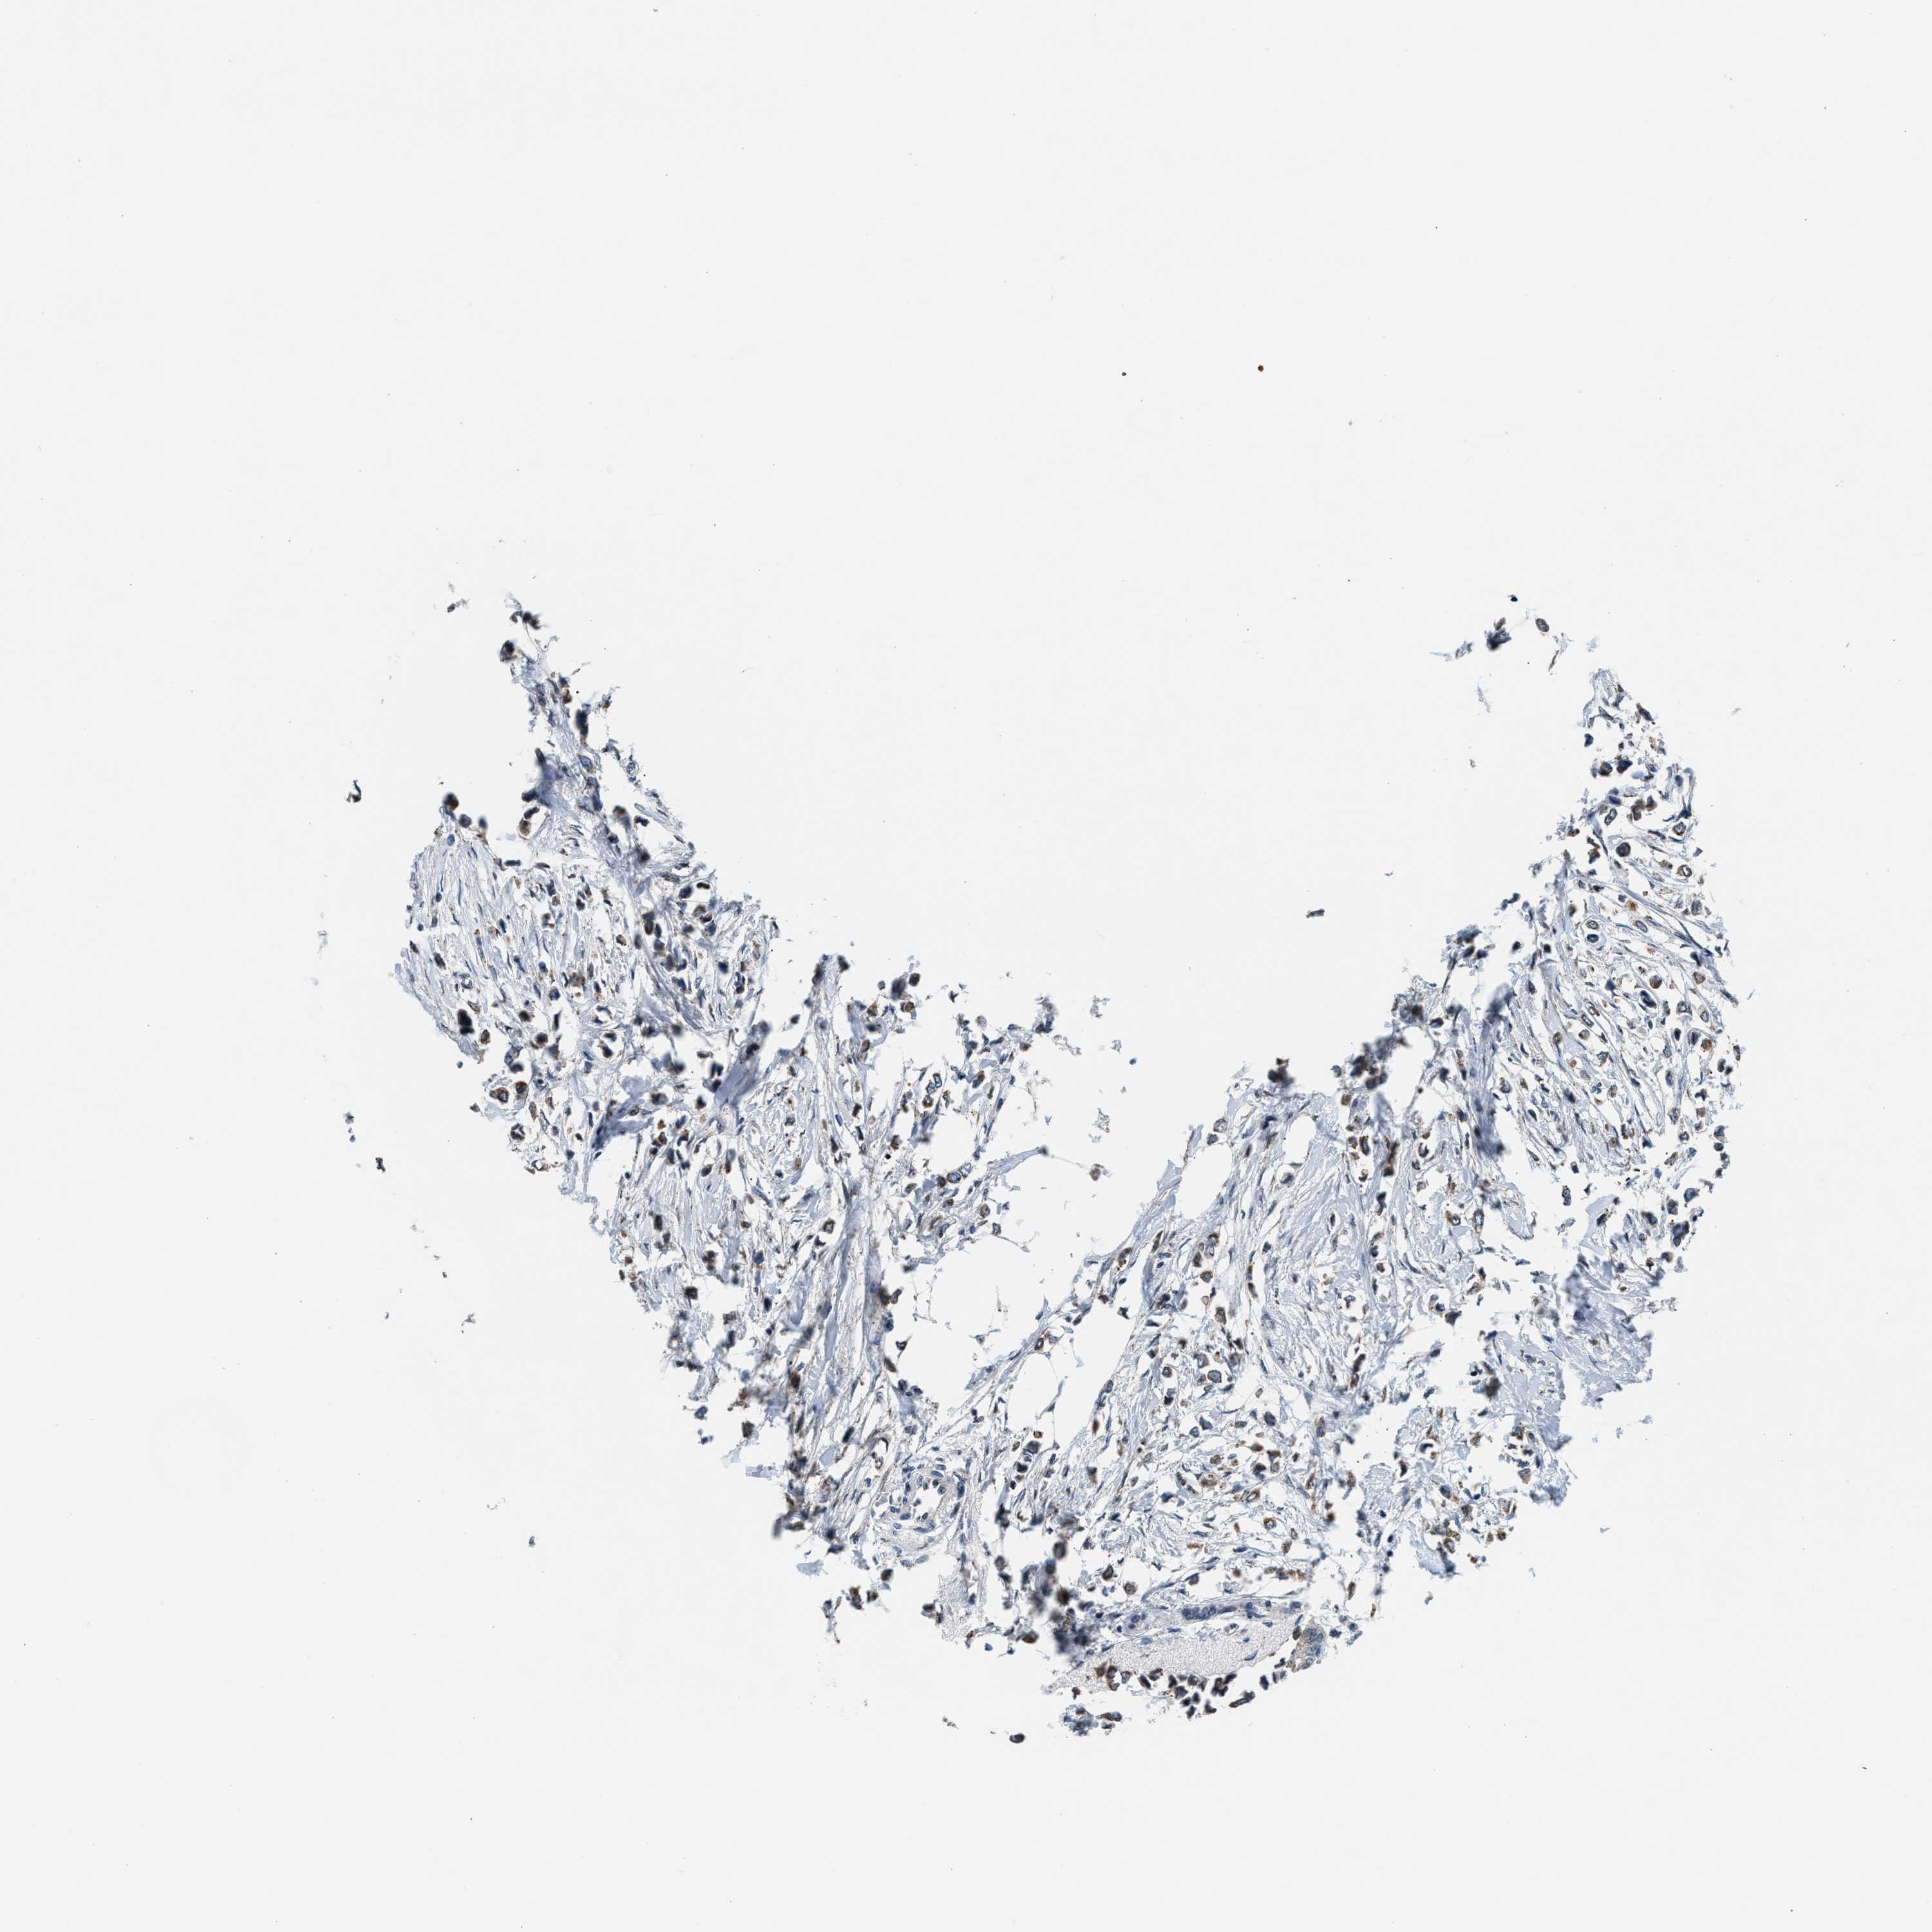

CANCER BREAST CANCER Show tissue menu

BRCA TCGA BRCA VALIDATION PROTEIN EXPRESSION